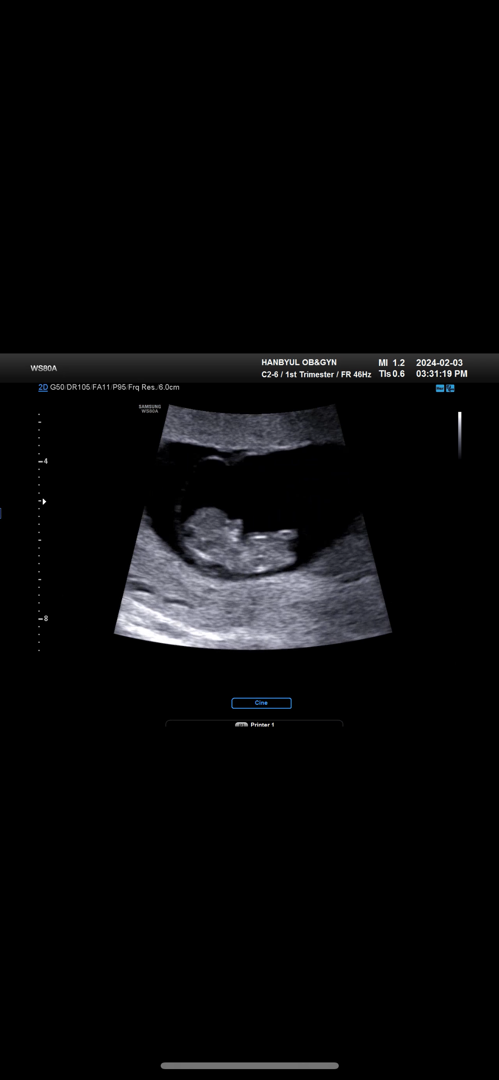

9주2일 춈파

너무 파닥파닥 심소잡기 애 먹었다능,, 코 근처에 있는게 손인데 손가락 까지 다 보여줬어요 넘 귀여움😭